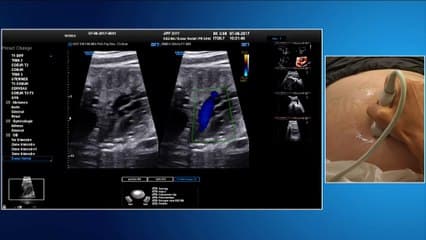

La médiathèque du Collège Français d'Échographie Fœtale (CFEF) constitue l'une des plus importantes collections de ressources vidéo dédiées à l'échographie fœtale en France. Avec plus de 3 261 vidéos, elle couvre l'ensemble des thématiques liées à la pratique échographique prénatale.

Vous y trouverez des conférences présentées lors des congrès nationaux et internationaux, des cours magistraux dispensés par des experts reconnus, des démonstrations pratiques sur des cas cliniques réels, ainsi que des podcasts et tables rondes sur les dernières avancées de la spécialité.